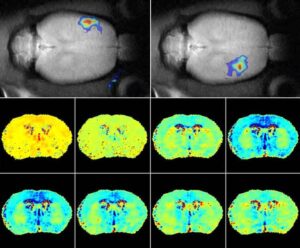

Ridurre la temperatura corporea a 34 gradi argina i danni cerebrali post-ictus e gli effetti collaterali delle terapie È un...